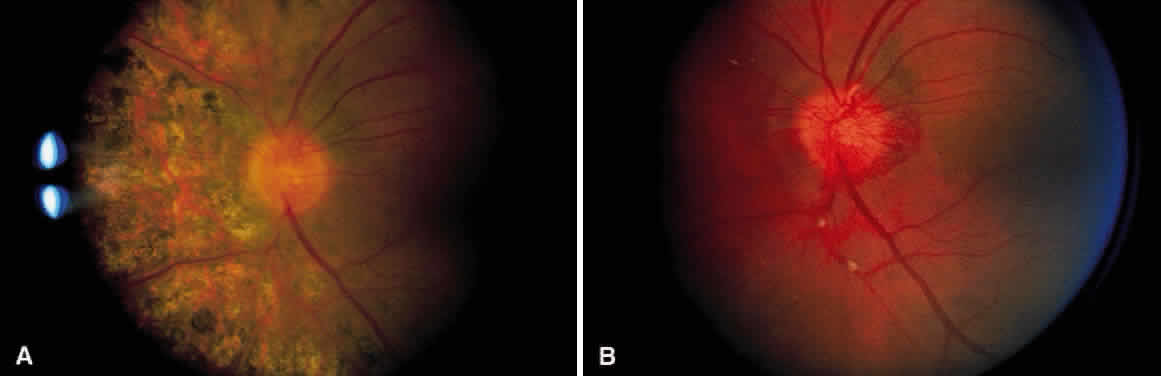

As a result of the retinal nonperfusion, new vessels can form either on the disc (neovascularization of the disc) or, more commonly, neovascularization can occur elsewhere in the retina (Fig. 5). These abnormal blood vessels can hemorrhage and are the major cause of visual loss in this disease. The neovascularization in the peripheral retina usually occurs at the junction of perfused and nonperfused retina, similar to the appearance of neovascularization in the peripheral retina in diabetic retinopathy and the other peripheral proliferative retinopathies. Neovascularization can be associated with extensive fibrovascular proliferation and fibrosis (Fig. 6). The anteroposterior and tangential traction resulting from the fibrovascular proliferation places these eyes at risk for development of retinal detachment. Neovascularization of the iris also has been described.

Fig. 6. Hypovascular fibroproliferation emanating from the disc. Usually, the vascular component of this proliferation is less prominent than that seen in the other proliferative retinopathies. Notice the tractional retinal detachment.

Henry Eales offered his patients a mixture of laxative, digitalis, and belladonna. Other remedies have included vitamin C, thyroid extract, and high-dose steroids. Because of the previously reported association with tuberculosis (TB), empirical anti-TB therapy is used in India.5 None of these treatments have been conclusively beneficial. Laser photocoagulation is the treatment of choice for the neovascularization of Eales' disease.1112 Numerous investigators have demonstrated regression of neovascularization with light-intensity scatter photocoagulation applied to the nonperfused peripheral retina and to the junction of perfusion and nonperfusion (Fig. 7). Vitrectomy can be used for removing persistent vitreal hemorrhages and fibrosis, often with good results.13 No treatment is known to prevent or reverse the nonperfusion or capillary dropout.

Fig. 7. A. Neovascularization of the disc. Notice the segmental exudative arteriolar sheathing. B. Same patient as in Figure 7A, 2½ years later. The patient had regression of the neovascularization after treatment with scatter photocoagulation of nonperfused retina. Areas of arteriolar sheathing previously observed are no longer present.